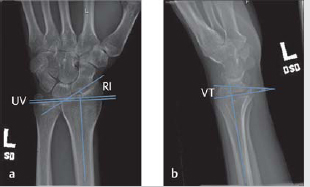

Medoff published average radiographic parameters of the distal radius from a sample size of 40, including radial inclination (23.6 degrees), radial height (11.6 degrees), and volar tilt (11.2 degrees). 8 The normal radiographic parameters of the distal radius are shown in ► Fig. 8.1 (normal wrist X-ray with overlying parameters).